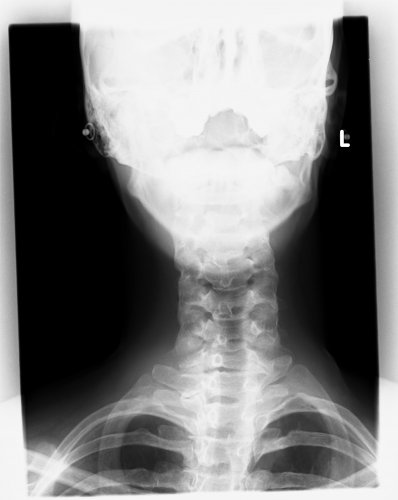

Jetzt so seit 2 Wochen habe ich tierische Schmerzen vom Ncken und den kompletten Rücken runter,ich bin also doch zum Arzt gegangen, da wurde dann alles komplett vom Rücken geröngt,die Bilder hab ich aber noch nicht gesehen. Beim Arzt war ich nur ganz kurz drin, er meinte nur es ist schlimm aber nicht zu spät. Hat mir jetzt Physio - und Ergotherapie verschrieben mit Massage und Reizstrom. Das beginnt nun alles nächste Woche.